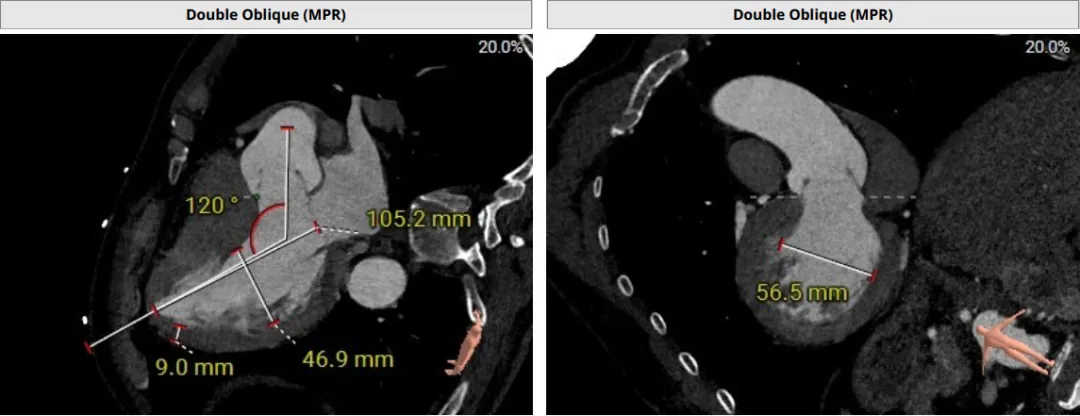

术前评估

该患者术前CT评估提示:主动脉瓣Type-I型,瓣叶稍增厚,左右冠窦瓣叶交界粘连,无冠窦瓣叶轻微钙化,存在三个瓣窦,分布不均匀,左右冠窦融合;主动脉瓣环周长折算直径32.6mm;左心室流出道周长折算直径32.0mm,无钙化,无狭窄;STJ直径36.2mm,升主动脉直径38.6mm;左侧冠脉10.4mm ,瓣叶长10.8mm;右侧冠脉18.7mm,瓣叶长11.2mm;双侧冠脉开口高度可,无钙化;心尖-主动脉夹角偏大,左室主动脉夹角为120°;